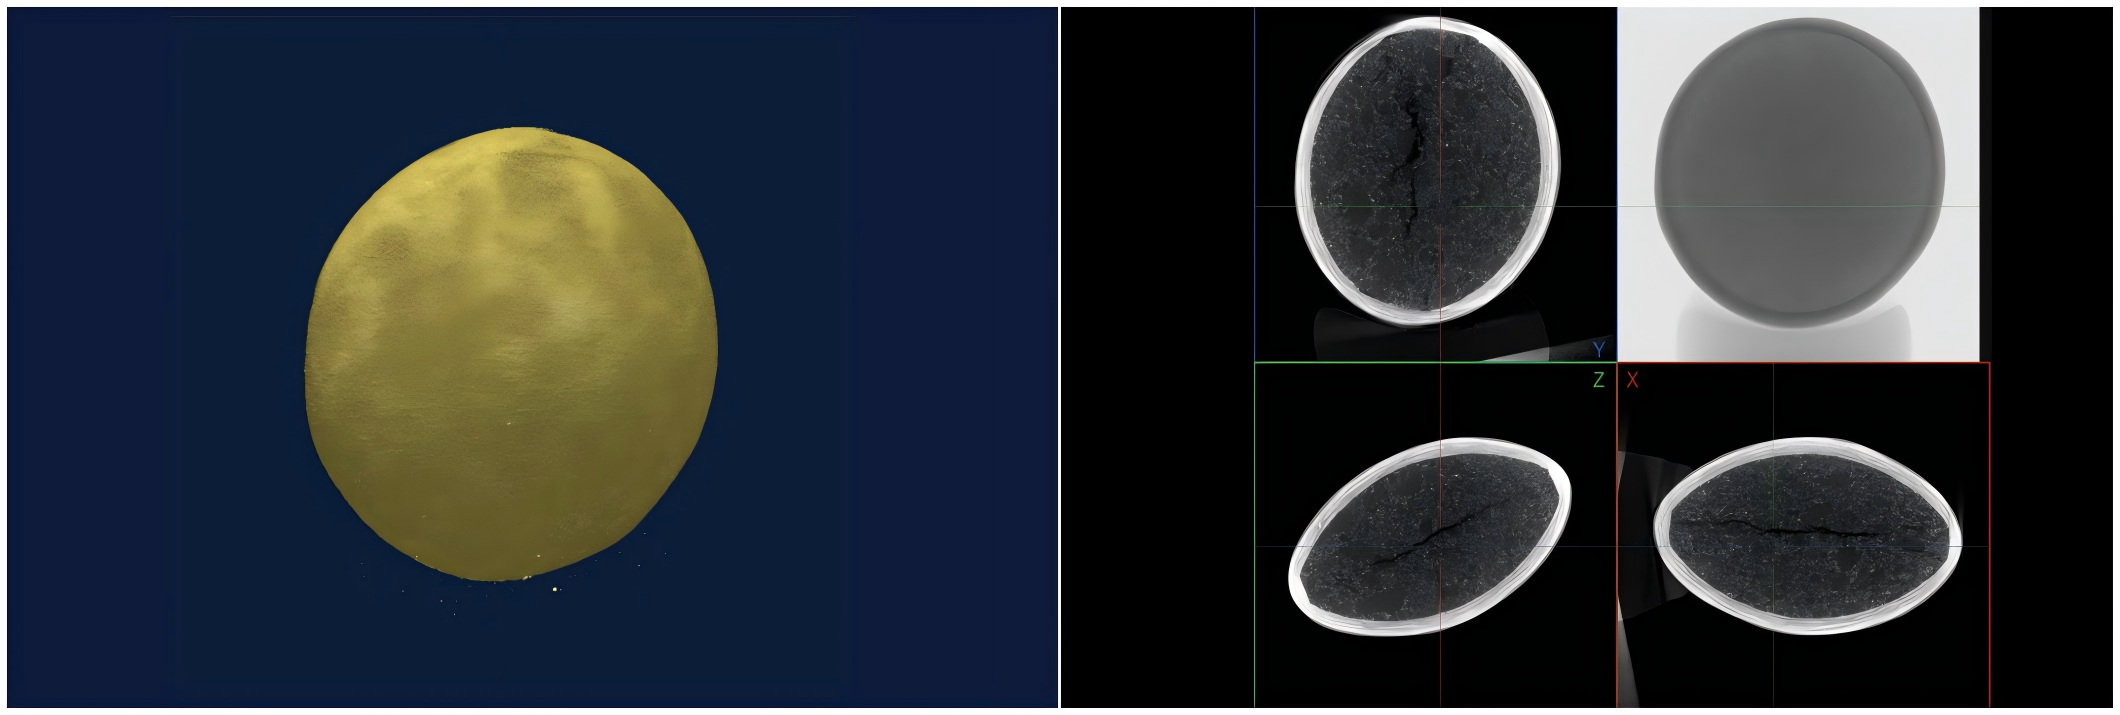

NEOSCAN N80 高分辨台式显微 CT 扫描以 6μm 像素大小扫描布洛芬片,可显示表层包衣、内部裂纹等内部结构信息。

NEOSCAN N80 高分辨台式显微 CT 以 6μm 像素大小扫描抗过敏药盐酸西替利嗪片,表层包衣和内部结构清晰可见。